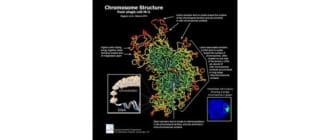

強力な最先端技術を使用して、研究者たちは初めて、染色体の真の3D構造がぼんやりと歪んだX形から遠く離れていることを明らかにしています。彼らは、実際には複雑で、むしろ美しいです。 英国のBabraham Institute […]